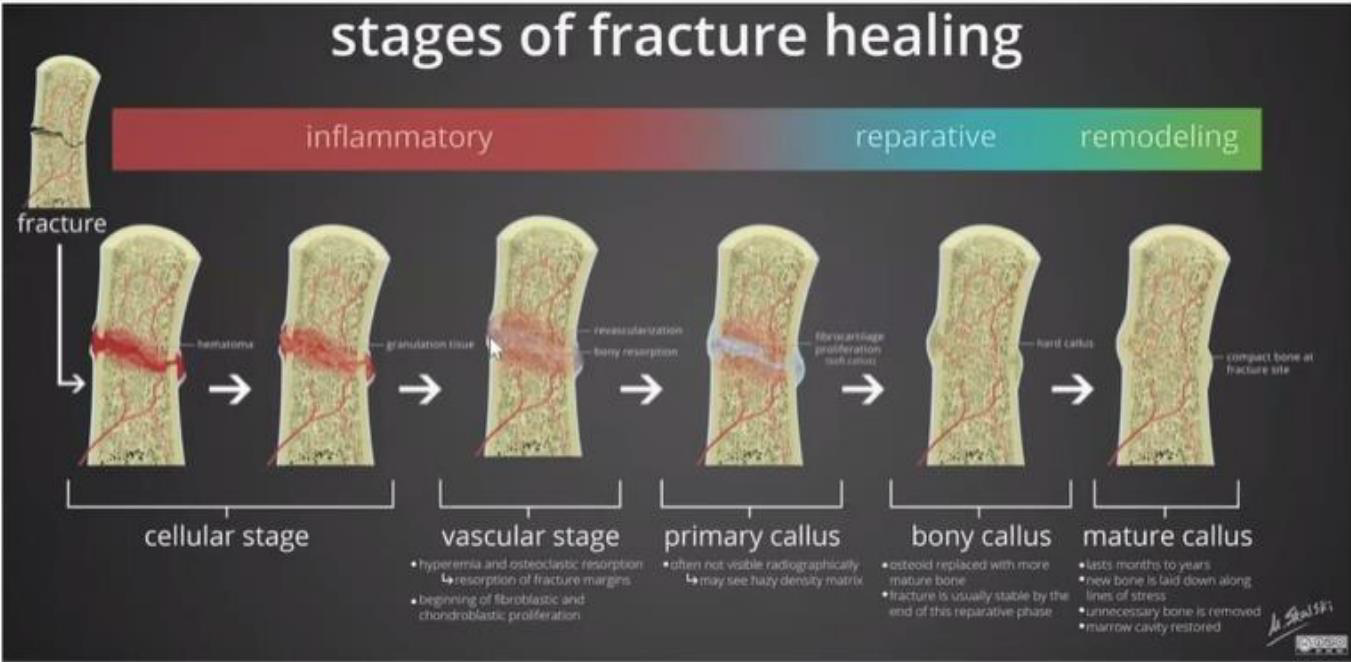

拔牙窩的癒合

| 時間階段 | 組織變化與重點 | |

|---|---|---|

| Day 0 | 血塊形成/止血 | 血塊除了止血外,內含許多 growth factor,會釋放訊號誘發骨形成。 |

| Day 4~5 | 血塊轉為 granulation tissue | 持續釋放 growth factor,並伴隨更多鈣化物形成。 |

| Day 5~16 | 轉變為 connective tissue matrix | 拔牙窩的 bundle bone 開始吸收,讓周圍骨髓空間的血管增生,逐漸形成 cancellous bone。 |

| Week 3~6 | 骨生成與軟組織屏障 | woven bone 從拔牙窩周邊開始形成。 |

| Week 5~10 | 骨重塑形成 trabecular bone | 傳統觀念認為骨頭鈣化至此階段後才適合植牙。 |